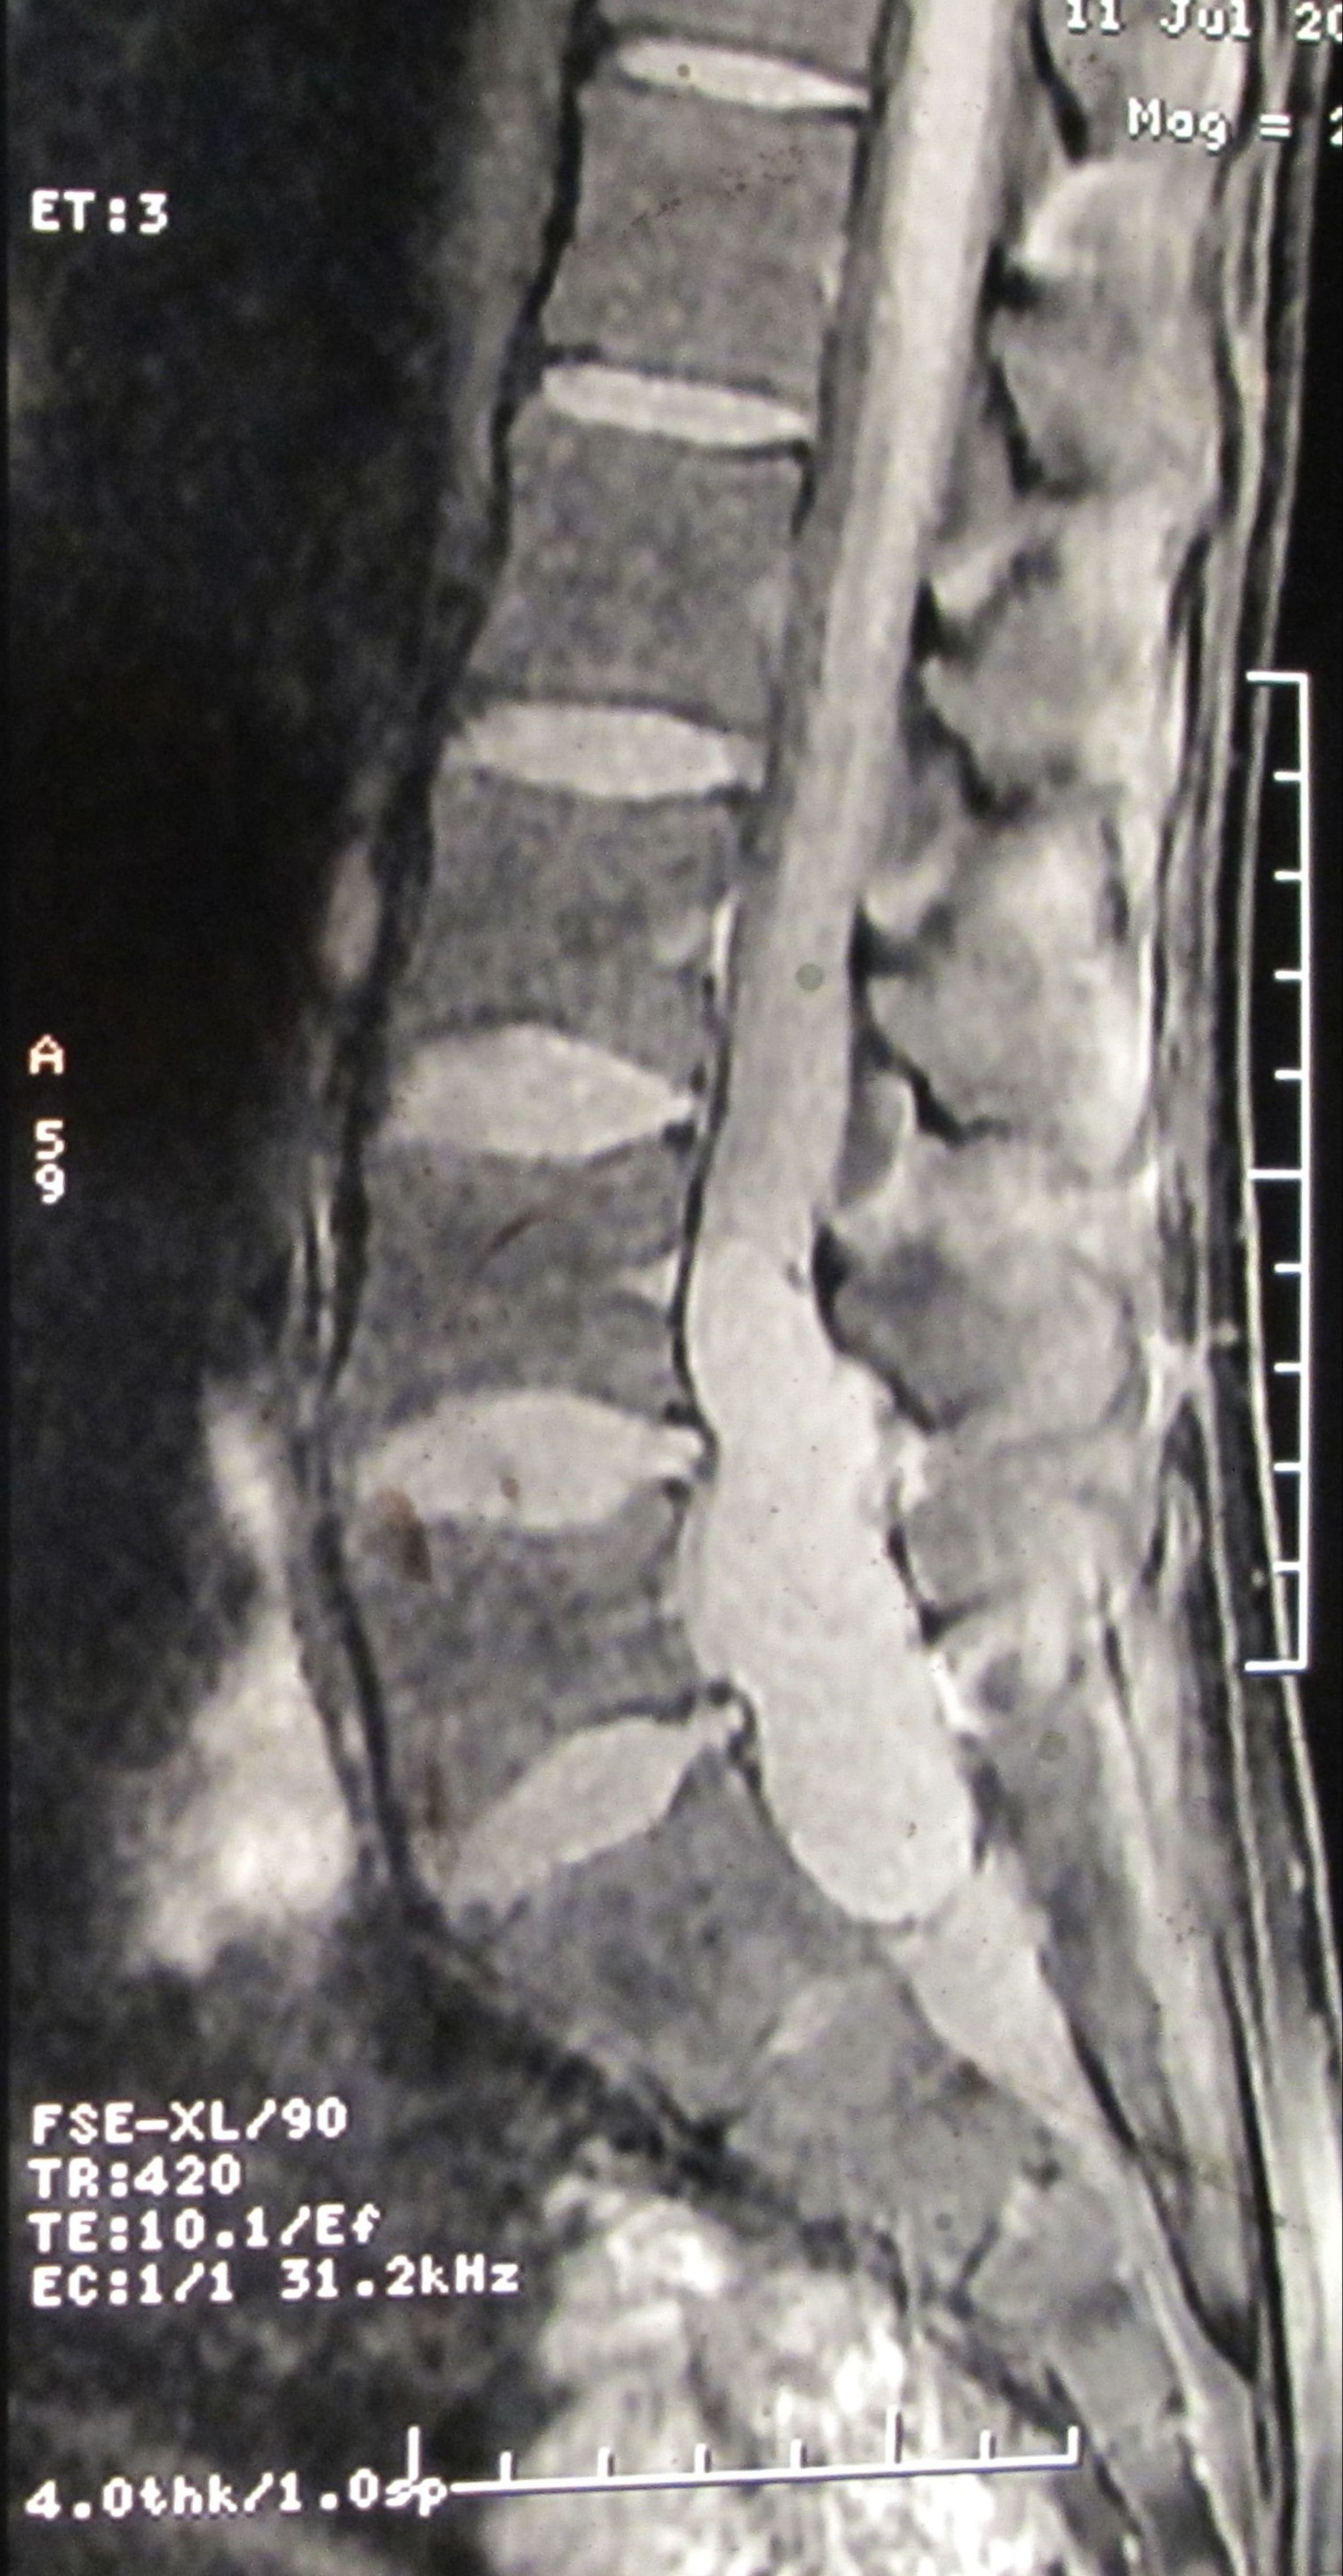

Filum terminale paraganglioma is a rare tumour with usual short segment spinal involvement (one or two segments) as described in various literatures. It can also present with long segment spinal involvement as in our case, the tumour has involved L4 to S1 segments. Prognosis of filum terminale paraganglioma is excellent after total excision as it is classified under WHO grade I tumor. Nonetheless, after subtotal removal, tumour recurrence can occur. Even such an extremely rare entity with a larger spectrum of presentation can be treated successfully by total removal of the tumour. Here we present a fi lum terminale paraganglioma which was diagnosed after histopathology and immuno-histochemistry. Patient made a full recovery after tumour removal.